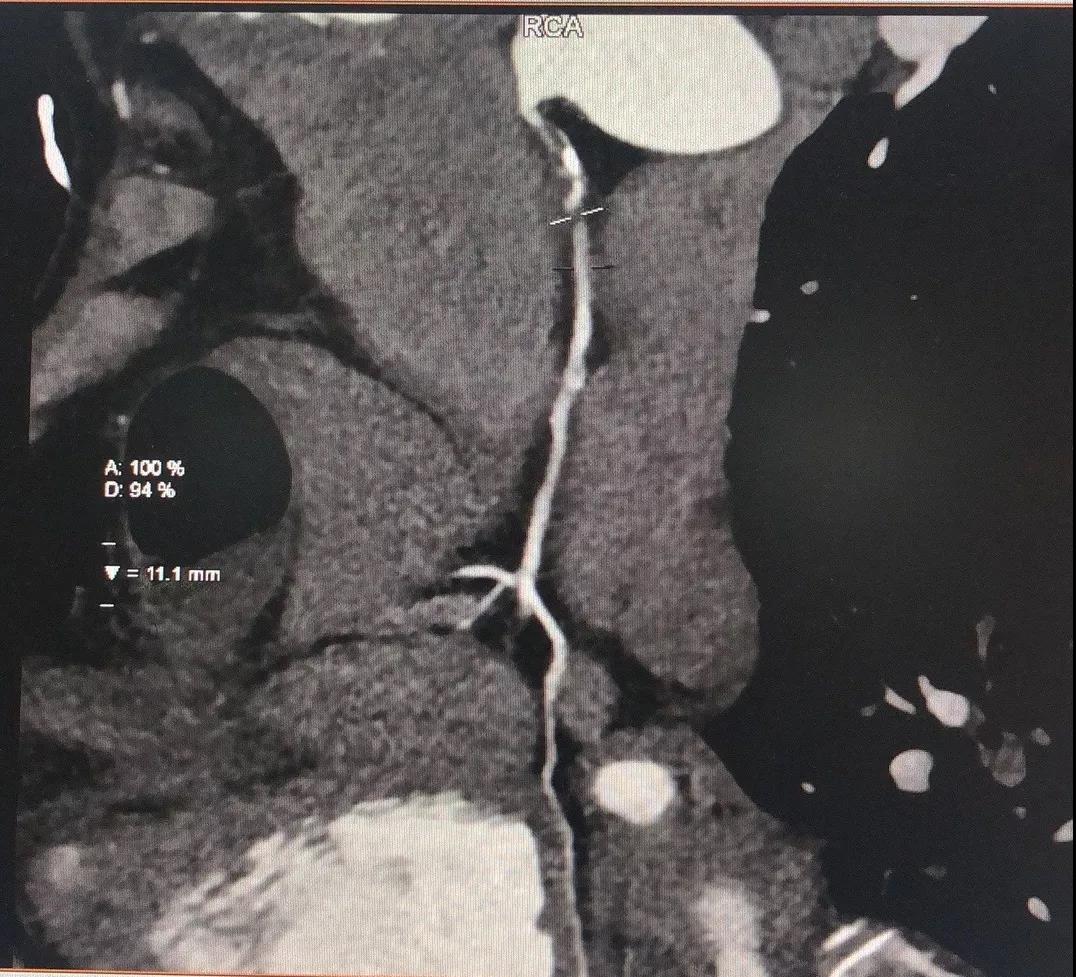

关于RCA

RCA CTA特点

1、入口清楚;

2、闭塞段长度小于20cm;

3、闭塞段血管无明显扭曲;

4、闭塞段内有两处明显的钙化斑块;

5、闭塞出口处血管相对比较“健康”;

6、侧枝血管汇入左室后支;

7、后三叉处的血管相对比较“健康”。